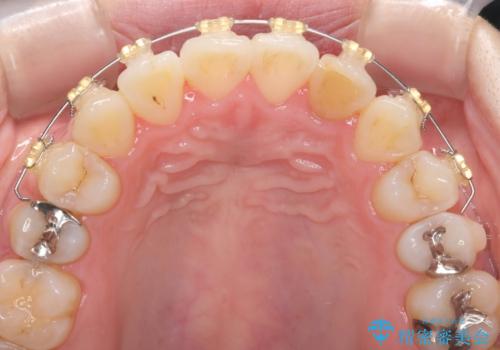

引っ込んだ前歯を並べたい マウスピースと部分ワイヤーのコンビネーション矯正

- 引っ込んで生えてしまっている前歯を並べたい、と矯正治療を希望され来院されました。

まずマウスピース矯正インビザラインシステムで、引っ込んだ歯が並ぶためのスペースを作ったのち、部分ワイヤー矯正を行い短期間での配列を計画します。

マウスピース・ワイヤーそれぞれの長所をうまく活かすことで治療期間の短縮が可能となります。

このように前歯の部分ワイヤーは引っ込んでしまった前歯や がたつきを素早く改善することができます。